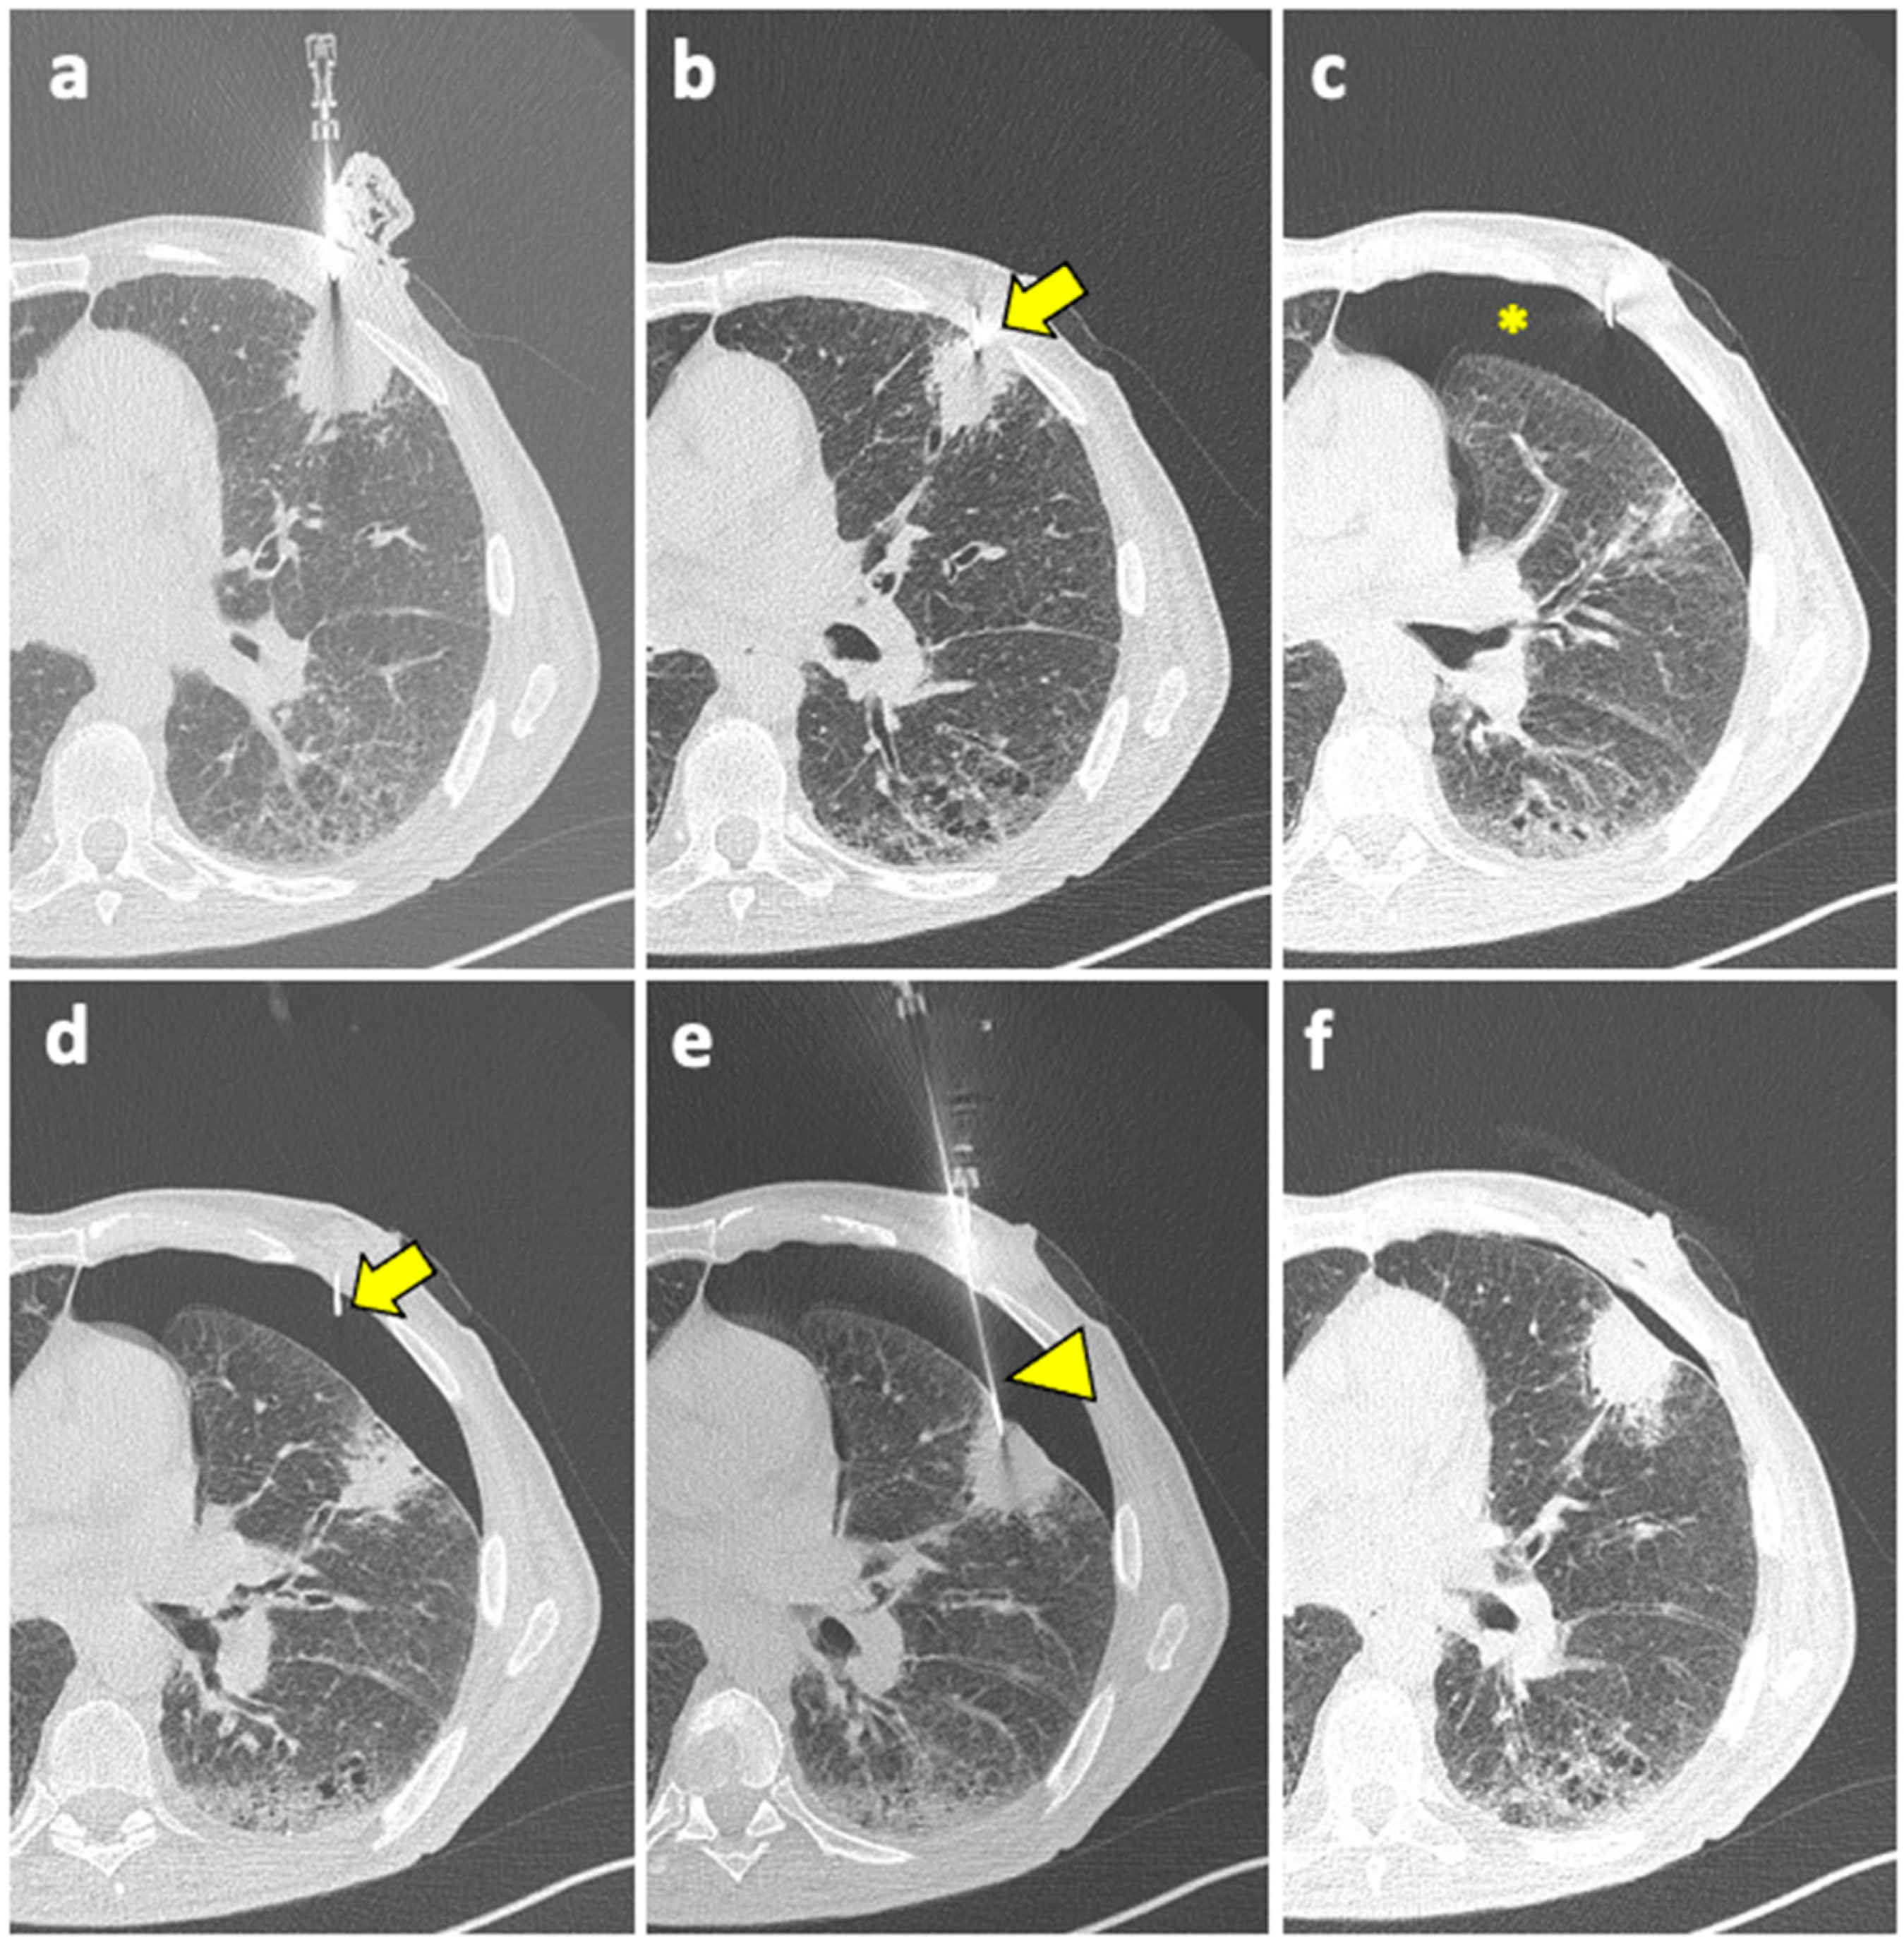

Patient with moderate–severe PNX and/or breathlessness require active intervention, with simple aspiration being suggested as initial treatment [91]. If still in place, the coaxial cannula used for the biopsy can be retracted back into the pleural space and used for aspiration; otherwise, it can be reinserted near the biopsy site. An example of manual aspiration is shown in Figure 2.

Figure 2.

(a) A coaxial needle is pointed under CT guidance towards a solid mass in the left upper lobe of a 61-year-old man with history of COPD, smoking, and follicular lymphoma. (b) The tip of the needle (arrow) is pushed forward into a juxta-plural position. (c) At the following CT scan, pneumothorax is detected (asterisk). (d) The coaxial needle is pushed slightly forward into the air space (arrow), the stylet is removed, and the cannula is connected to a syringe for manual aspiration. (e) At the same time, a new, longer coaxial needle (arrowhead) is positioned into the target lesion across the pneumothorax, and a core needle biopsy is performed (histology: diffuse large-B-cell lymphoma). (f) Final CT scan after manual aspiration shows significant reduction of the pneumothorax; patient had stable vitals during follow-up and did not require a chest tube insertion. Abbreviations—COPD: chronic obstructive pulmonary disease; CT: computed tomography.

Manual aspiration is efficient at preventing PNX advancement because it creates an apposition between the visceral and the parietal pleura. When PNX develops despite manual aspiration, a chest tube is needed [85]; a small-bore catheter (10–14 F) should be placed for chest drainage [84,91].